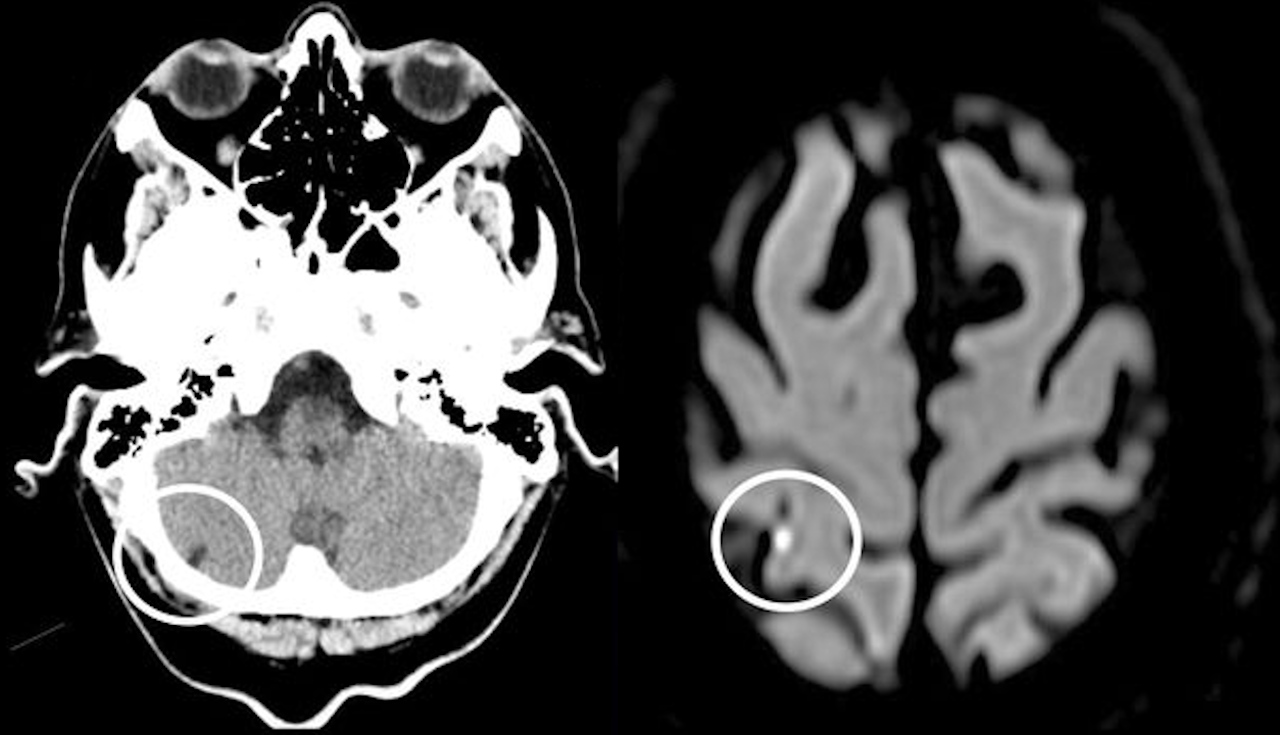

Інфаркт у мозочку (зліва) та інсульт у тім'яній частці (справа) мозку чоловіка. Ronnevi & Moreira / BMJ Case Reports, 2025

Вдруге потрапив до лікарні чоловік після того, як відчув нудоту, запаморочення та труднощі з фокусуванням зору через постійний зсув його поля. У пацієнта не виявили порушення роботи черепних нервів, зокрема пов’язаних із рухом очей, а також симптому Бабінскі, який вказує на порушення зв’язку кори головного мозку зі спинним мозком. Магнітно-резонансна томографія мозку вказала на ішемічний інсульт із невизначеним джерелом крововиливу в тім’яній частці, яка відповідальна за обробку візуальної та просторової інформації. У три місяці після виписки чоловік пережив ще декілька невеликих безсимптомних інсультів, але після правильного вибору ліків уже не мав порушень зору та руху.